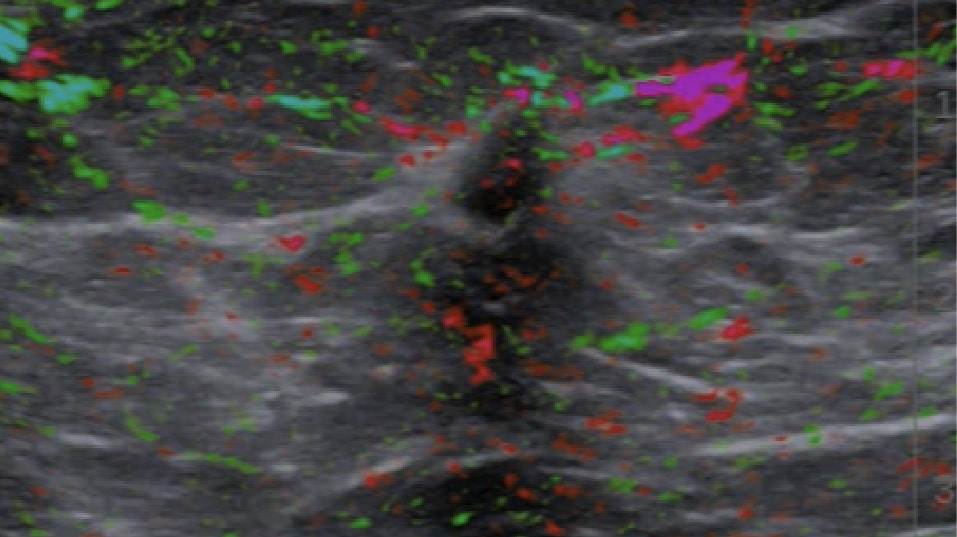

See oxygenated blood in a sample Imagio® scan

In general, malignant masses are more vascular and deplete oxygen from the blood at a higher rate than do benign masses. The two wavelengths of laser light used in the Imagio® system facilitate imaging by showing the relative differences between oxygenated and deoxygenated blood.

See deoxygenated blood in a sample Imagio® scan